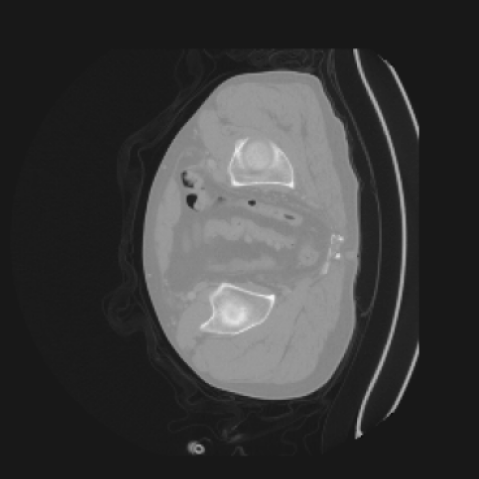

The motivation for this work arises from the need to address these limitations in the synthesis of 3D medical images. Current techniques do not produce high-resolution 3D images that preserve spatial coherence and capture the full complexity of medical data, as shown in Figure 2, 5. The development of advanced 3D generative models tailored specifically for medical imaging could not only improve the quality of synthetic medical images but also help alleviate data scarcity, enhance privacy protection, reduce computational requirement and ultimately advance the use of deep learning in healthcare applications.

To demonstrate the advantages of 3D semantic image synthesis over 2D semantic semantic image synthesis, we conducted a detailed comparison with the SegGuidedDiff [26] model. SegGuidedDiff generates medical images based on 2D semantic maps, producing individual 2D slices that are later stacked to form a 3D image. However, this approach has limitations in capturing spatial continuity and coherence across slices, which is critical for representing the spatial structure of 3D medical images. As a result, inconsistencies often arise between different slices, particularly in preserving anatomical structures across the coronal and sagittal planes. The generated images exhibit varying levels of denoising, resulting in differences in brightness and sharpness across the images. This inconsistency in denoising can lead to noticeable variations in visual quality, where some regions appear clearer and others less distinct.

As shown in Figure 5, the generated slices exhibit high consistency across adjacent slices. The anatomical structures and semantic patterns are smoothly and coherently preserved between slices, indicating that our model is capable of generating 3D-consistent synthetic images rather than isolated 2D slices.